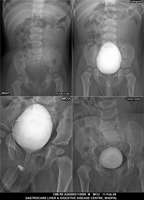

Section: URETHROGRAM

Total: 95 Cases